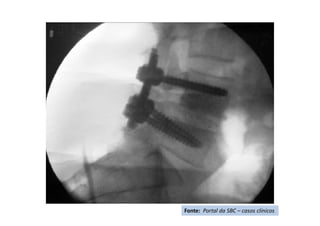

• Cifose pós-traumática

• Resumo do caso: Queda da própria altura com diminuição de força de

membros inferiores de forma gradativa.

• Paciente (dados): Sexo feminino, 54 anos

• História: Queda da própria altura durante internação hospitalar em outro

serviço para tratamento de crise de ativação do LES há 6 meses. Apresentou

diminuição de força de membros inferiores de forma gradativa. Foi avaliada

no serviço de origem e realizado TC e aventada a hipótese de mielite

transversa. Foi encaminhada ao CRER para reabilitação. Nesse momento

apresentava apenas parestesia em MMII e FM grau 0 (ASIA B).

• Diagnóstico(s): Consolidação viciosa de T5, com cifose pós-traumática e

compressão medular (ASIA B)

• Antecedentes de Lúpus (LES), uso crônico de corticóide e tabagismo severo

• Tratamento(s): Realizada vertebrectomia com descompressão medular e

reconstrução com Mesh CAGE e artrodese de T2 a T8 por via posterior.

• Seguimento ("Follow up"): PO 1 ano com boa melhora funcional da

paciente.

• Resultado Final: Paciente apresentou melhora gradativa da força muscular e

da função, estando hoje com força muscular grau IV em MMII, conseguindo

deambular e inclusive subir e descer escadas com apoio (ASIA D).

Fonte: Portal da SBC – casos clínicos

RX – Pós-operatório 4 meses